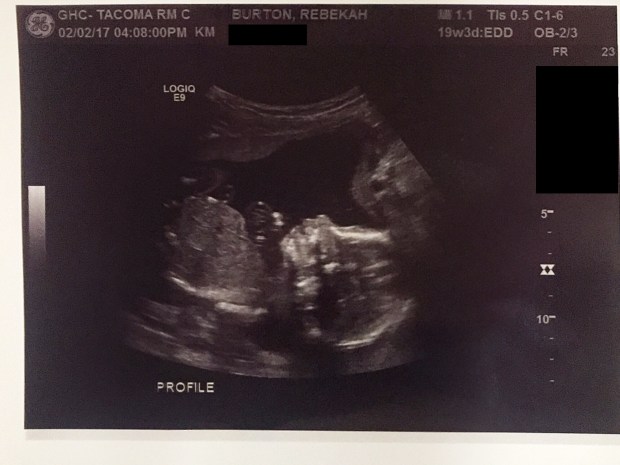

Here’s the most recent pics of Baby Girl!

Profile

Profile – the curved thing above her nose is her hand and fingers curled up